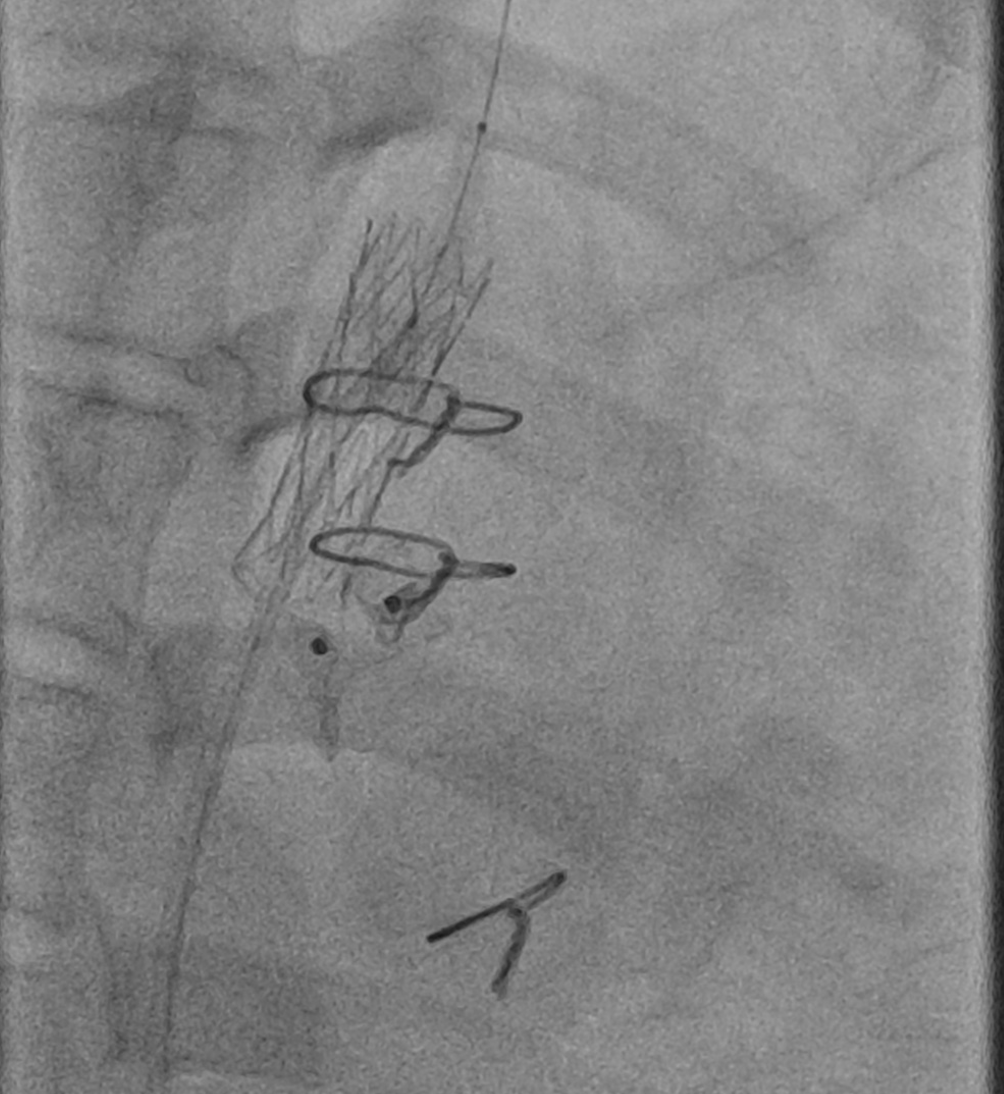

Firstly, an angiography was performed to confirm the positions of the CoA stent and PDA device. A 0.014” microwire (Transcend, Boston Scientific) was used to cross through the PDA device to reach the upper part of the aorta. A 5F guiding catheter was advanced toward the proximal stent but was unsuccessful. To assist with advancing the 5F guiding catheter, we used a 3.0 mm and 5.0mm balloon to dilate the opening beside the PDA device. An angiography was then conducted to assess the relative positions of the CoA stent and PDA device. We decided to deploy an additional stent to cover the distal part of the previous stent to direct the PDA device towards the pulmonary artery. A 7F delivery system was advanced to the optimal position, and a 21L AndraStent was successfully deployed. A 8.0mm high-pressure balloon (VACS III) was then used to further dilate the stent. The pressures in the ascending and descending aorta (below the stent) were recorded as 115mmHg and 90mmHg, respectively. Finally, an angiography confirmed the correct positioning of both the stent and the PDA device without complications.